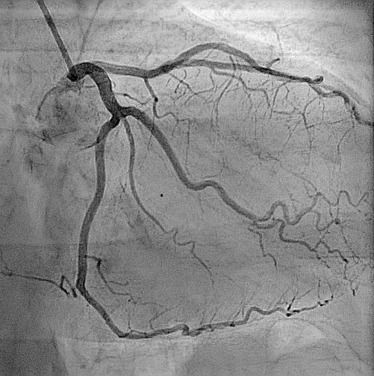

Angiography Karar haider abd al hussein